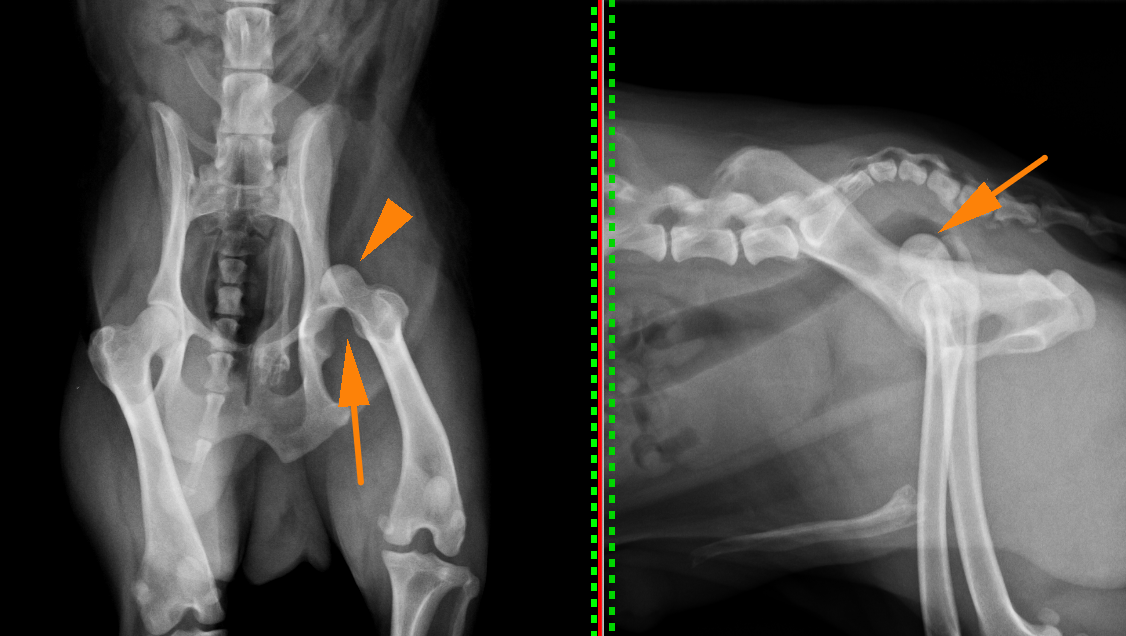

股関節脱臼

股関節とは骨盤の寛骨臼と呼ばれる凹みの部分に、大腿骨の大腿骨頭と呼ばれる球状の骨がはまることで関節しています。それが外傷や、寛骨臼の形成不全などによって抜けてしまうことを股関節脱臼といいます。

股関節が脱臼すると強い疼痛を引き起こし、足を地面に着けることができなくなり挙上してしまいます。股関節脱臼は脱臼する向きによって大きく2つに分けられます。90%が頭背側脱臼というもので、前方かつ、上方に脱臼してしまうタイプです。残りの10%が尾腹側脱臼というもので後方かつ、下方に脱臼してしまうタイプです。治療には用手による整復と、手術による治療がありますが、用手による整復の成功率は非常に低いとされており、基本的に手術によって整復します。頭背側脱臼ではワッシャーによる固定またはトグルピン法、骨頭切除などの術式が選択できます。症例によって治療法を選択しますが、可能であれば骨頭を切除せずに戻すのが理想と言えます。骨頭を切除すると術後の機能回復に時間がかかるのと、機能が元のの70〜80%にとどまると言われているからです。